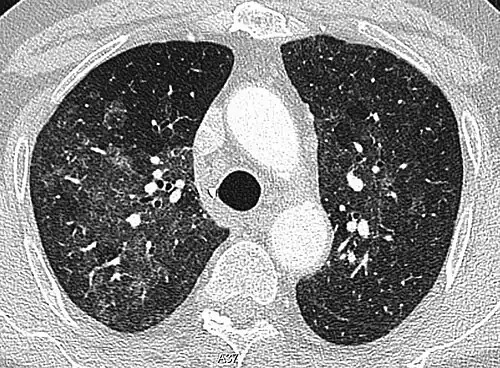

High-resolution CT image showing ground-glass opacities in the periphery of both lungs in a patient with COVID-19 (red arrows). The adjacent normal lung tissue with lower attenuation appears as darker areas.

Ground-glass opacity is among the most common imaging findings in patients with confirmed COVID-19.[16][17] One systematic review found that among patients with COVID-19 and abnormal lung findings on CT, greater than 80% had GGOs, with greater than 50% having mixed GGOs and consolidation.[16] GGOs with mixed consolidation has most often been found in elderly populations.[18] Several studies have described a pattern among initial, intermediate, and hospital discharge imaging findings in the disease course of COVID-19. Most commonly, initial CT imaging reveals bilateral GGOs at the periphery of the lungs. During initial stages, this is most often found in the lower lobes, although involvement of the upper lobes and right middle lobe has also been reported early in the disease course.[16][18] This is in contrast to the two similar coronaviruses, SARS and MERS, which more commonly involve only one lung on initial imaging.[19][20] As the COVID-19 infection progresses, GGOs typically become more diffuse and often progress to consolidation.[11][18] This is sometimes accompanied by the development of a crazy paving pattern and interlobular septal thickening.[18] In many cases the most severe pulmonary CT abnormalities occurred within 2 weeks after symptoms began.[17] At this point, many individuals begin showing resolution of consolidation and GGOs as symptoms improve. However, some patients have worsening symptoms and imaging findings, with further increase in septal thickening, GGOs, and consolidation. These patients may develop lung "white-out" with progression to acute respiratory distress syndrome (ARDS) requiring treatment escalation.[17][21]